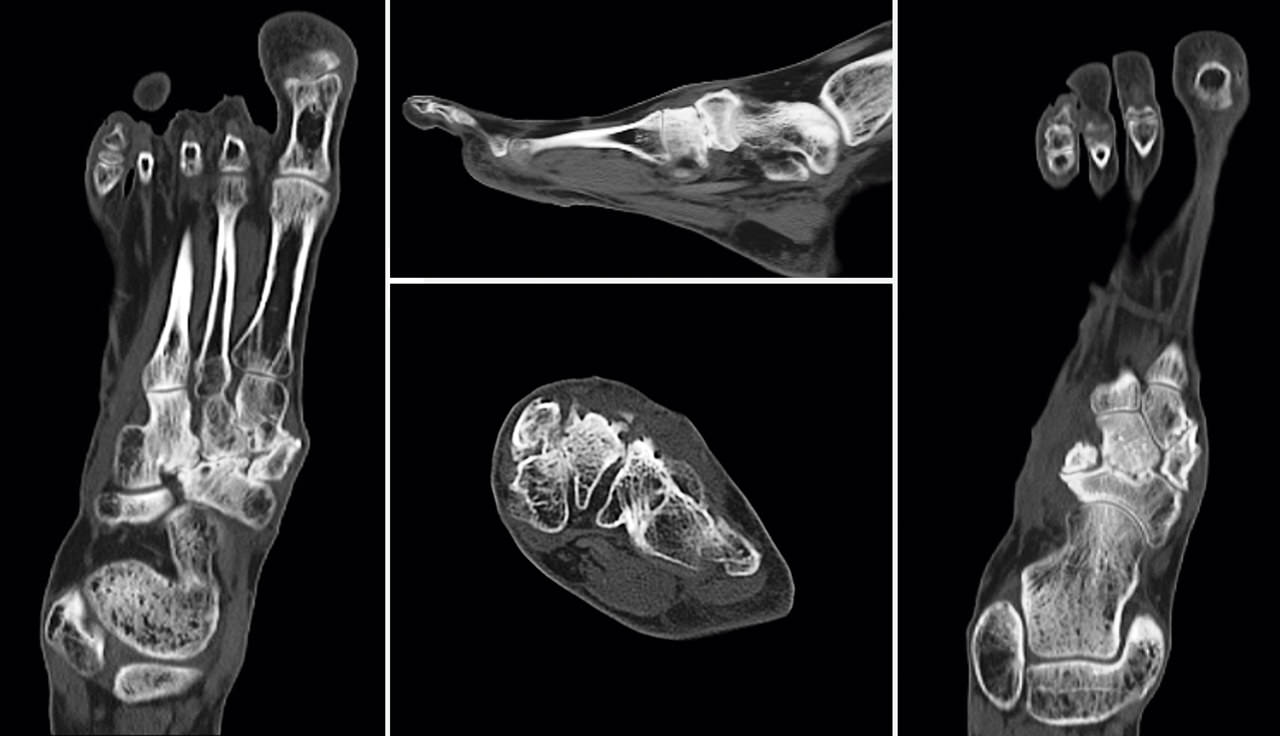

Se realizó estudio mediante tomografía computarizada (TC) (Figura 3) donde podemos ver la falta de fusión de la osteotomía de la primera cuña, los cambios degenerativos escafocuneanos, la fusión de la tercera cuña con el cuboides y el hundimiento de la columna medial a nivel transcuneano.

Figura 3. Imágenes de la tomografía computarizada.